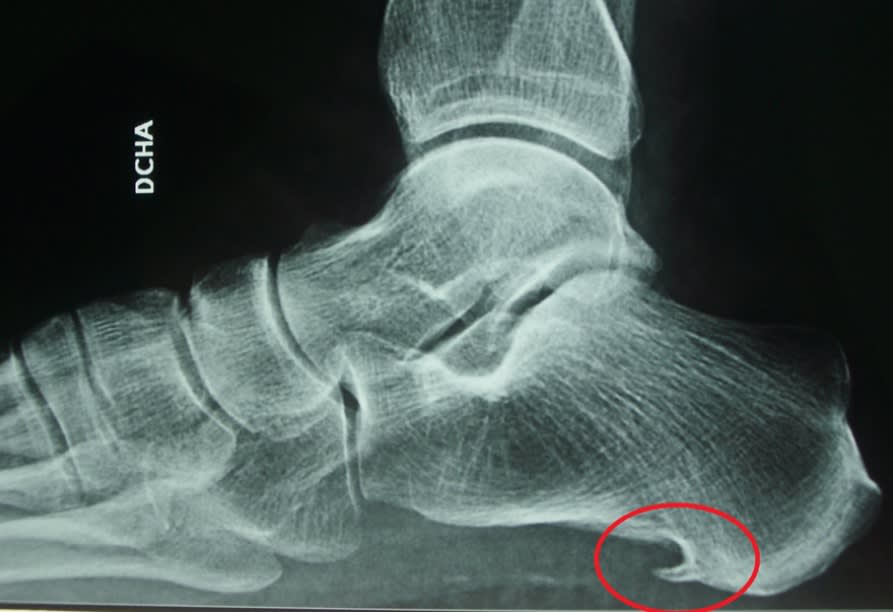

Cuando se produce un crecimiento irregular en el hueso del talón y viene acompañado de dolores por inflamación, estamos ante un caso de espolón en el talón o espolón calcáneo. Es decir, se trata de calcificaciones producidas en el talón identificadas por su forma triangular o en forma de lanza.

Estos crecimientos óseos suelen estar asociados con la fascitis plantar, una condición donde el tejido conectivo en la planta del pie se inflama. Aunque la causa exacta de la formación de espolones no siempre es clara, se cree que factores como la biomecánica anormal del pie, el uso excesivo, lesiones repetitivas o malos hábitos de calzado pueden desencadenar su desarrollo.